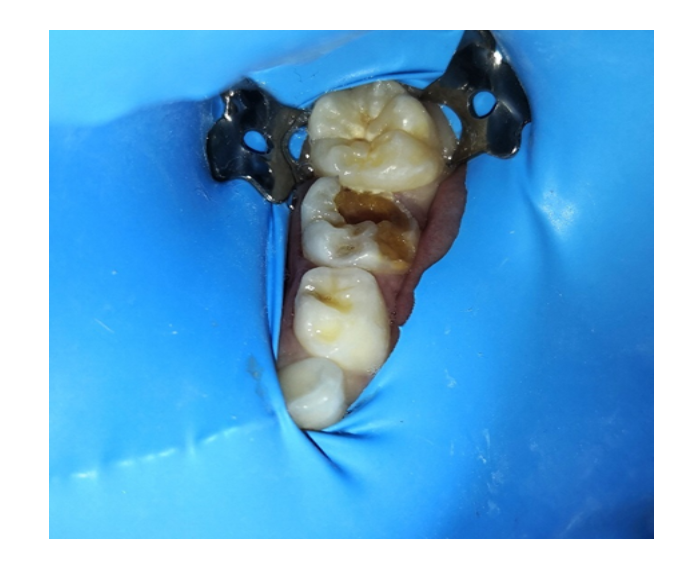

Selladores

/Resinas